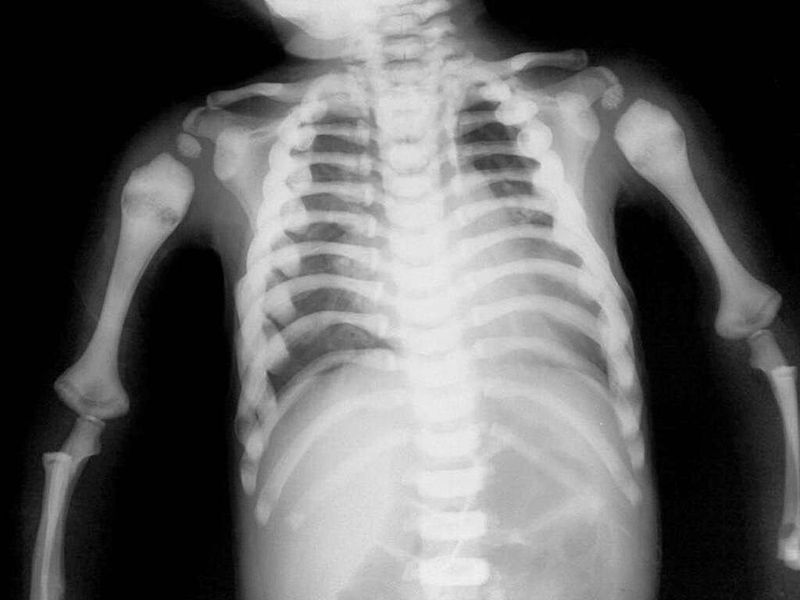

Osteopetrosis literally means "stone bone". This hereditary disorder results from defective osteoclasts and overgrowth of bone which makes bones to become sclerotic and thick, but their abnormal structure results in them being both weak and brittle, which increases the likelihood of fractures. The x-ray above shows relatively thickened and dense ribs, humerus and vertebrae. Patients may suffer from anemia, recurrent infections, and hepatosplenomegaly due to bone expansion leading to bone marrow narrowing and extramedullary hematopoiesis.Treatment is with bone marrow transplant and resultant normalisation of bone production.